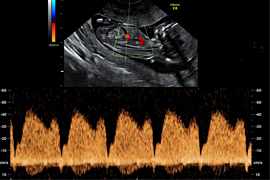

Blutfluss im Ductus venosus

• Muster des Blutflusses in einem fetalen Blutgefäßes (Ductus venosus)

Blutfluss in mütterlichen Gefäßen

Durch die Messung der Blutflussmuster über den mütterlichen Gefäßen kann – in Kombination mit den mütterlichen Hormonwerten, der mütterlichen Vorgeschichte sowie dem mütterlichen Blutdruck – das Risiko für eine Präeklampsie und eine Wachstumsstörung berechnet werden. Ergeben sich auffällige Werte kann durch spezielle Überwachung und vorbeugende Maßnahmen (Gabe von Acetylsalicylsäure-ASS) das Risiko für die Entstehung einer Präeklampsie und für eine Frühgeburt erheblich gesenkt werden.

Die Geschwindigkeit des Blutflusses und der Widerstand in den Blutgefäßen lassen sich in der Doppler-Ultraschalluntersuchung messen.

Dopplersonographie

Blutflussmessung

Bei der Dopplersonographie werden Blutgefäße dargestellt und die Strömungsgeschwindigkeit des Blutes gemessen. So können die zuführenden mütterlichen Gefäße (Gebärmutterarterien) und die kindlichen Gefäße (z.B. Nabelschnurarterien, Hirnarterien, Venen) untersucht werden. Hierdurch ist es einerseits möglich, eine Risikobewertung für eine Wachstumsstörung beim Kind oder für die Entwicklung mütterlicher schwangerschaftsbedingter Erkrankungen vorzunehmen. Andererseits kann das kindliche Wohlergehen bei Auffälligkeiten sehr zuverlässig bestätigt und überwacht werden.